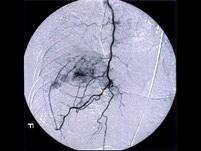

问题 微小肝癌主要通过哪项检查确定()

选项 A.AFP测定 B.B超检查 C.选择性肝动脉造影 D.放射性放射性核素肝扫描 E.MRI检查

答案 C